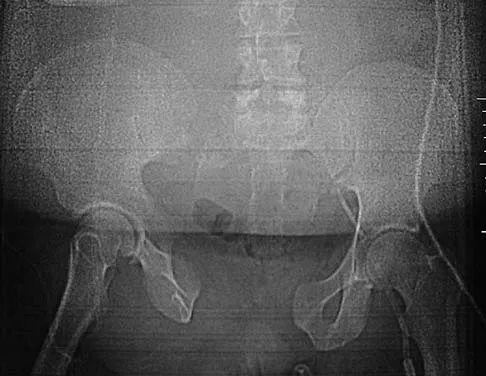

Figure 2a shows the radiograph of a 48-year-old man who was involved in a motorcycle accident. A CT scan is shown in Figure 2b. The patient underwent pelvic angiography for persistent hypotension despite resuscitation. What vessel is most likely to be injured?

Explanation

The pelvic injury is a severe anterior-posterior compression III or Tile C injury. The vessel most likely injured is the superior gluteal artery, but several arterial bleeding sources are likely. Vertical shear injuries can also injure this vessel, but it is much less common. When arterial injury follows a lateral compression injury, it is usually related to injury of a more anterior vessel like the obturator artery or a branch of the external iliac artery. O'Neill PA, Riina J, Sclafani S, et al: Angiographic findings in pelvic fractures. Clin Orthop 1996;329:60-67.